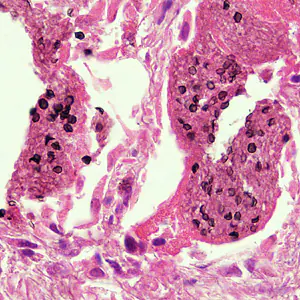

Pneumocystis jirovecii trophozoites.

The specific diagnosis is based on identification of P. jirovecii in bronchopulmonary secretions obtained as induced sputum or bronchoalveolar lavage (BAL) material. In situations where these two techniques cannot be used, transbronchial biopsy or open lung biopsy may prove necessary. Microscopic identification of P. jiroveci trophozoites and cysts is performed with stains that demonstrate either the nuclei of trophozoites and intracystic stages (such as Giemsa) or the cyst walls (such as the silver stains). In addition, immunofluorescence microscopy using monoclonal antibodies can identify the organisms with higher sensitivity than conventional microscopy.